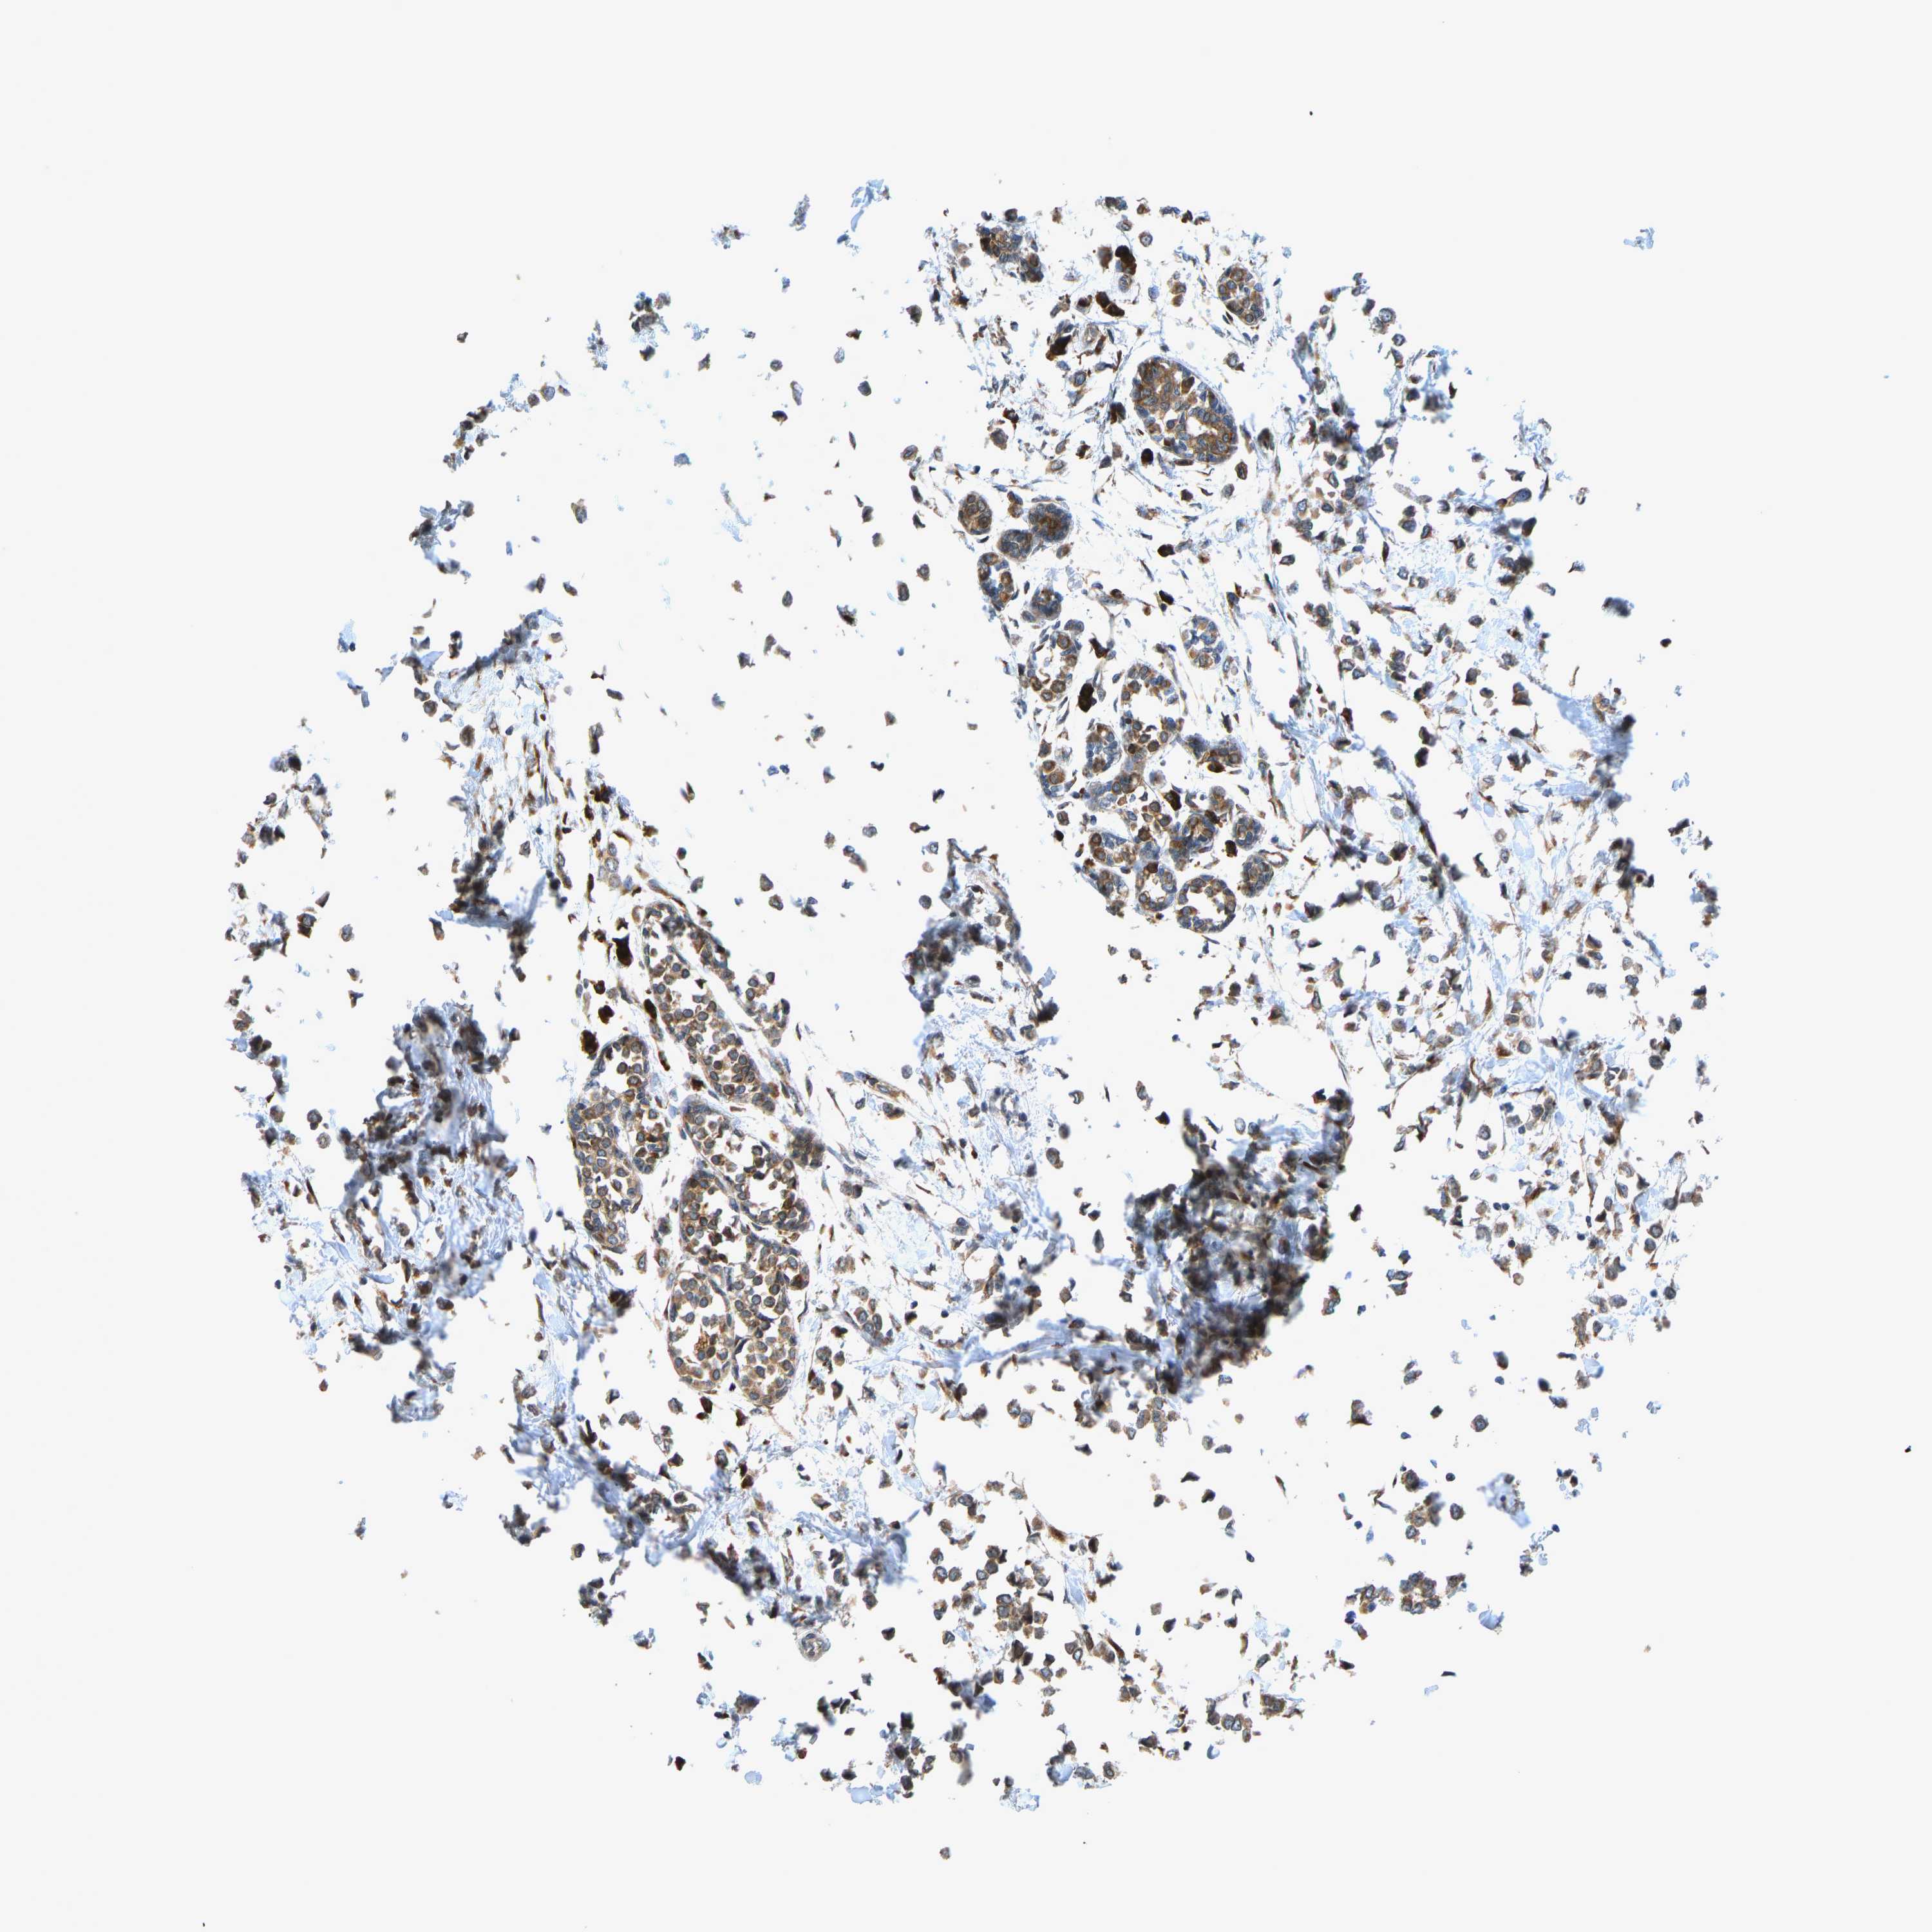

CANCER BREAST CANCER Show tissue menu

BRCA TCGA BRCA VALIDATION PROTEIN EXPRESSION

Breast cancer

Human cancer